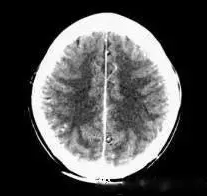

(機器故障偽影:常為環(huán)形或同心圓狀高密度偽影)

2、機器故障偽影的形狀機器故障所至偽影的形狀各種各樣,有非同心圓形和同心圓形(單同心圓和多同心圓、直線形、柵格形條紋狀)、星狀,還有不規(guī)則形,一般來說.根據(jù)偽影形狀可大致區(qū)分為機器哪一個系統(tǒng)故障所致。

如:單同心圓可能為通道板故障、連續(xù)屏蔽多個通道,多同心圓可能為環(huán)境溫濕度變化較大,AD控制板故障、線性電源問題、高壓線性電源問,滿屏斜條或直線可能為高壓系統(tǒng)故障·不規(guī)則形則可能為球管老化所致。